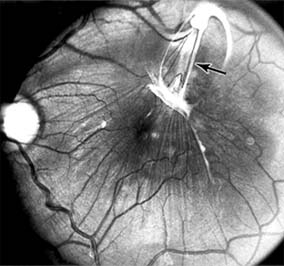

MACULAR HOLE

A macular hole is a partial or full-thickness absence of the sensory retina in the macula. This disorder occurs most often in elderly women and is associated with elevated plasma fibrinogen levels. The typical finding on biomicroscopy of the symptomatic eye is a full-thickness, round or oval, sharply defined hole measuring one-third disk diameter in the center of the macula, which may be surrounded by a ring detachment of the sensory retina (Figure 10-11). With a full-thickness macular hole, visual acuity is impaired and metamorphopsia, as well as a central scotoma, are present on the Amsler grid. An operculum of retinal tissue may overlie the macular hole. Tangential traction from epiretinal vitreous cortex plays an important role in the pathogenesis of macular hole. Early stages of macular hole formation, such as a deep foveal yellow spot or ring, may be reversible as the posterior vitreous cortex spontaneously separates from the retina. Therapy for macular hole disease involves reattaching and potentially restoring function to the retina overlying the cuff of subretinal fluid surrounding the hole. While the anatomic results of vitrectomy surgery to close macular holes are encouraging, the clinical benefits are still under study.

Figure 10-11

Figure 10-11: Macular hole (large arrows) with surrounding sensory retinal detachment (small arrows).